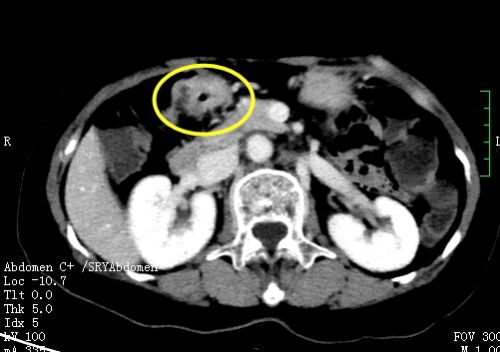

来自湖南岳阳县的刘女士今年69岁,3月前开始出现间断便血不适,在当地捷克论坛 做了腹部CT及肠镜活检后,考虑为结肠肝曲癌,后经多方打听来到捷克论坛结直肠肛门外科诊治,肖志刚主任接诊后将其收入院,并进行详细的术前检查评估。

经过精心的术前准备后,肖志刚主任团队为患者施行微创手术——腹腔镜下右半结肠癌根治+胆囊切除,经阴道取出标本的NOSES(VIII)手术。